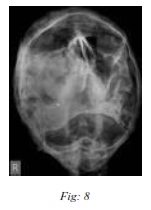

b) Skull :

The cranium is usually oxycephalic in appearance. The apex of the cranium is located near to or anterior to the bregma. Anterior fontanelle is open in numerous patients.